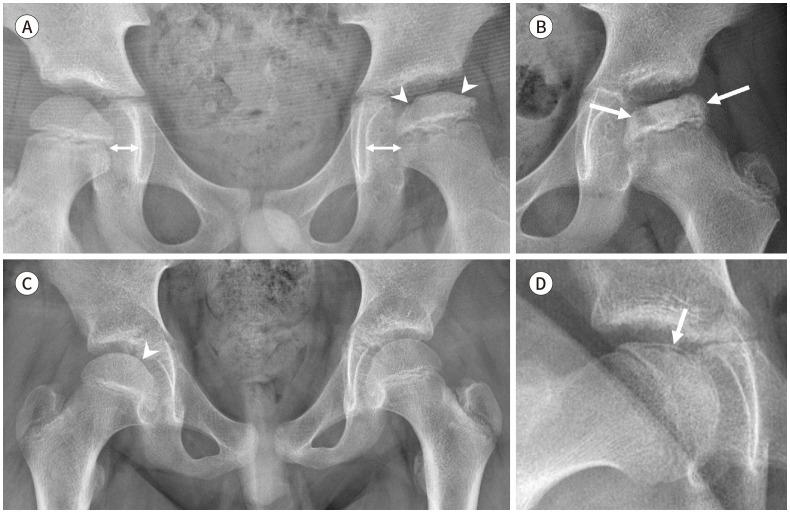

Developmental dysplasia of the hip is a condition characterized by hip joint instability due to acetabular dysplasia in infancy, necessitating precise ultrasound examination. Legg-Calvé-Perthes disease is caused by a temporary disruption in blood flow to the femoral head during childhood, progressing through avascular, fragmentation, re-ossification, and residual stages. Slipped capital femoral epiphysis is a condition where the femoral head shifts medially along the epiphyseal line during adolescence due to stress, such as weight-bearing. Differentiating between transient hip synovitis and septic arthritis may require joint fluid aspiration. Osteomyelitis can be associated with soft tissue edema and osteolysis. When multiple lesions are present, it is essential to distinguish between Langerhans cell histiocytosis and metastatic neuroblastoma. This review will introduce imaging techniques and typical findings for these conditions.

发育性髋关节发育不良是一种因婴儿期髋臼发育不良导致髋关节不稳定的病症,需要进行精确的超声检查。Legg-Calvé-Perthes病是由儿童期股骨头血液供应暂时中断引起的,历经缺血、碎裂、再骨化和残留阶段。股骨头骨骺滑脱是一种在青春期由于负重等压力导致股骨头沿骨骺线向内侧移位的病症。区分暂时性髋关节滑膜炎和化脓性关节炎可能需要进行关节液抽吸。骨髓炎可伴有软组织水肿和骨质溶解。当出现多个病灶时,区分朗格汉斯细胞组织细胞增多症和转移性神经母细胞瘤至关重要。本综述将介绍这些病症的影像学技术和典型表现。